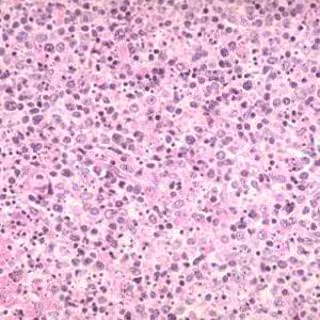

Los investigadores estudiaron células madre epiteliales de mama de humanos y ratones para desvelar por qué las células madre del cáncer son más resistentes a la radiación que otras células cancerígenas.

Estudios anteriores han mostrado que las células madre de la sangre tienen menores niveles de especies de oxígeno reactivo (ROS, según sus siglas en inglés) que el resto de células. Los investigadores se plantearon entonces que podría suceder lo mismo en las células madre epiteliales de mama. Descubrieron que las células madre de mama normales de ratones tenían niveles más bajos de ROS que aquellas que no eran células madre y que esta característica era compartida por las células madre cancerígenas tanto de humanos como de ratones.

Los científicos descubrieron por qué cuando examinaban los niveles de expresión genética las células madre del cáncer de mama humano producían en cantidades mucho mayores de proteínas antioxidantes que las otras células. Los antioxidantes neutralizan los ROS antes de que causen muchos daños. Esto podría explicar por qué las células madre de cáncer de mama en cultivo de ratones eran menos propensas que otras células a experimentar los daños en el ADN después de la radiación.